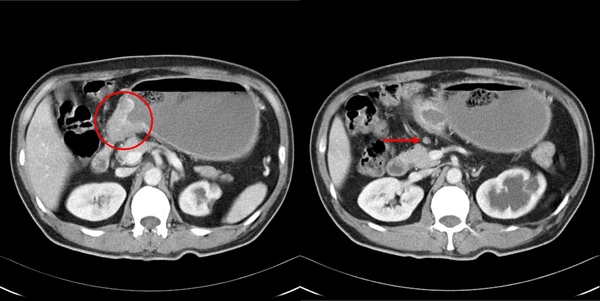

在電腦斷層裡,有時能見到胃癌在胃壁上形成一處凸起。

胃癌沿著淋巴結轉移相當常見,紅色箭頭處圓滾滾的淋巴結,有可能已有癌細胞轉移。

淋巴結轉移的狀況加劇後,電腦斷層裡便能見到胃周圍這許多不規則形狀的腫塊,都是癌細胞的轉移。